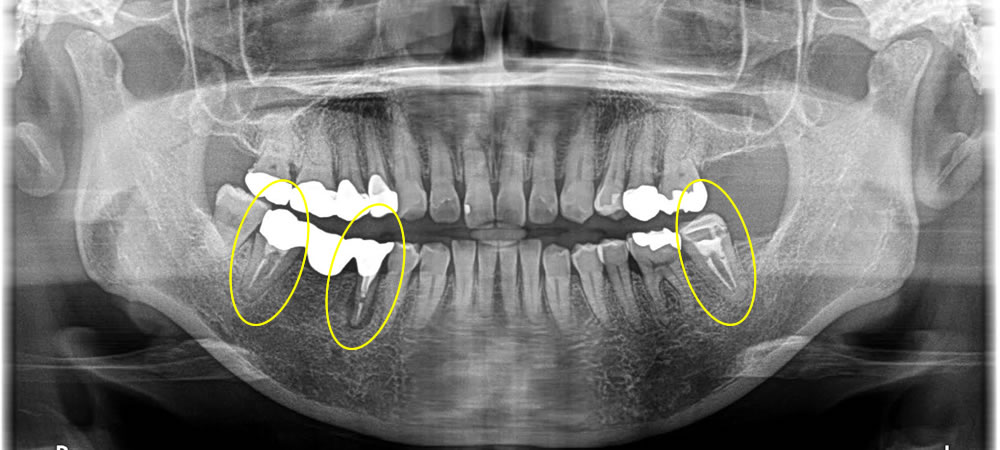

古い銀歯を除去しハイブリッドインレーで審美修復した症例

年齢

20代

性別

男性